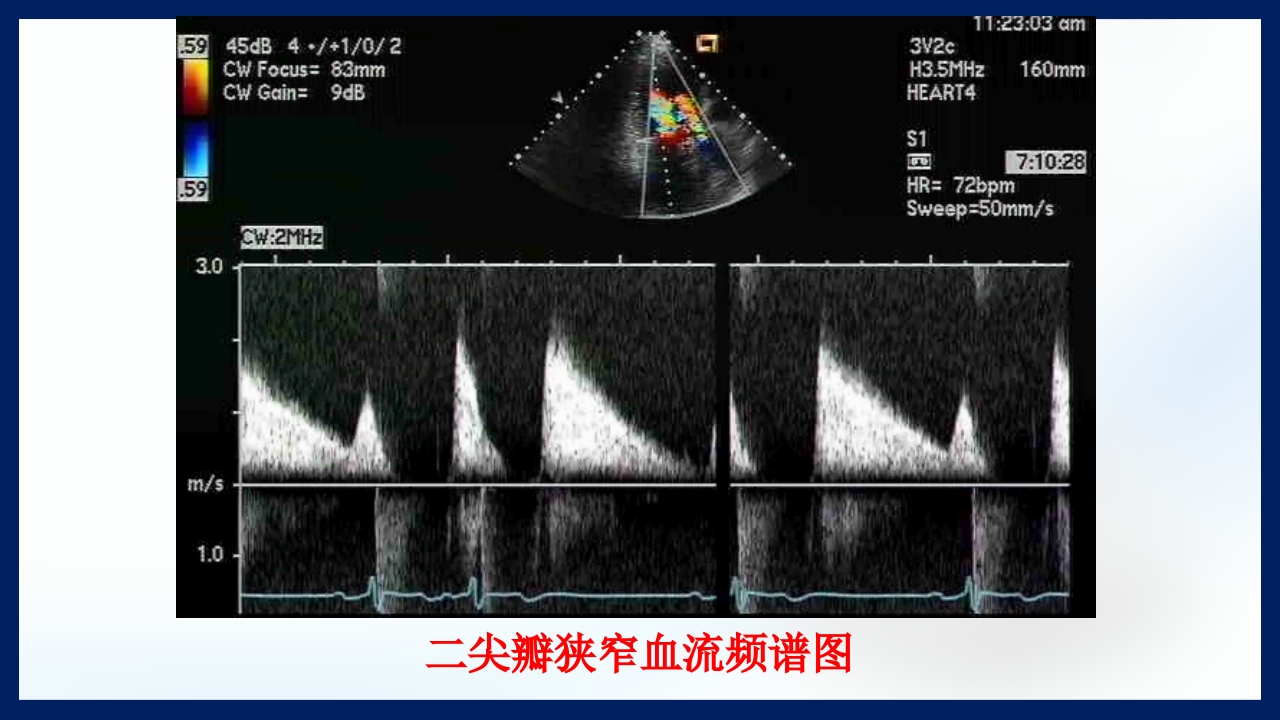

心 脏 瓣膜 医师:XXX 日期:20XX.XX.XX 讲授目的和要求 1 掌握二尖瓣和主动脉瓣膜病变的病理生理、临床表现及诊断方法。 熟悉二尖瓣和主动脉瓣膜病变的病因、鉴别诊断、并发症、治疗原则及 2 手术适应证。 3 了解瓣膜病的检查方法及治疗新进展。 心脏瓣膜病 是由于炎症、粘液样变性、退行性改变等原 因引起的单个或多个瓣膜结构的功能或结构异常,导致 瓣口狭窄及(或)关闭不全。二尖瓣最常受累,其次为 主动脉瓣。 (Rheumatic Heart Disease)简称风心病, 是风湿性炎症过程所致瓣膜损害,主要累及40岁以下人 群。 瓣膜粘液样变性和老年瓣膜钙化所致瓣膜病日渐增多。 3 瓣膜病分类 按病因分类: 风湿性、老年退行性、先天性、相对性 按受累部位和类型分: 二尖瓣狭窄、二尖瓣关闭...